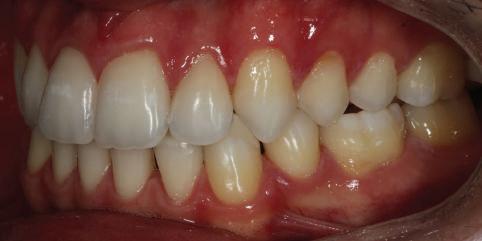

7Dental Tribune Bulgarian Edition / октомври 2022 г. Преди лечението Фиг. 1 Фиг. 4 Фиг. 7 Фиг. 10 Фиг. 13 Фиг. 16 Фиг. 17 Фиг. 18 Фиг. 19 Фиг. 20 Фиг. 11 Фиг. 14 Фиг. 12 Фиг. 15 Фиг. 8 Фиг. 9 Фиг. 5 Фиг. 6 Фиг. 2 Фиг. 3

8 Dental Tribune Bulgarian Edition / октомври 2022 г. По време на лечението Фиг. 21 Фиг. 25 Фиг. 30 Фиг. 31 Фиг. 34 Фиг. 38 Фиг. 40 Фиг. 44 Фиг. 48 Фиг. 50 Фиг. 49 Фиг. 46 Фиг. 39 Фиг. 41 Фиг. 45 Фиг. 47 Фиг. 42 Фиг. 43 Фиг. 35 Фиг. 36 Фиг. 37 Фиг. 32 Фиг. 33 Фиг. 26 Фиг. 28 Фиг. 29 Фиг. 27 Фиг. 22 Фиг. 23 Фиг. 24

9Dental Tribune Bulgarian Edition / октомври 2022 г. След лечението За авторите: Д-р Манол Ивчев е създател на COLDY DENT Functional Atelier, завършва дентална медицина във ФДМ, София. Шест години е стажант в ортодонтска практика. Интересите му са изцяло насочени към функционалната дентална медицина. Посещава курсовете на Доусън и Льо Гал. Преминава редица обучения, акредитирани от Института на Славичек във Виена – VieSID. Впоследствие става най-младият инструктор във VieSID. Придобива права да преподава философията на проф. Рудолф Славичек в България. В практиката си се придържа към протоколите на Славичек за функционално лече ние и диагностика, тъй като те са насочени към комплексно лечение. Завършва всички нива за морфология на зъбите и моделаж при Janos Mako. Повишава знанията си по функционална ортодонтия чрез индивидуален курс в Румъния. Д-р Ивчев е и сертифициран зъболекар по лингвална ортодонтия от Катедрата по ортодонтия от Университета по стоматология в Тегу, Южна Корея. Сертифициран е и за лечение на ортодонтски аномалии чрез миофункционални апарати, а също и за ортодонтия, подпомагана от миниимпланти, отново от Университета по стоматология в Южна Корея. Завършва индивидуално обучение по функционална ортодонтия в Университета по дентална медицина в Богота, Колумбия, както и индивидуално обучение по функционална ортодонтия и физиотерапия по про токола на Mariano Rocabado. Има завършено индивидуално обучение по функционална зъботехника и функционален Wax-Up клас I,II и III. Завършва курс за Digital Smile Design и Skin Concept в Люксембург при Christian Coachman, Florin Cofar, Paulo Kano, Josef Kunkela, Livio Yoshinagа. Зт. Leandro Gambogi, Бразилия, завършва зъботехника през 1999 г. Експерт и пионер в дигиталната диагностика. Лектор и инструктор на курсове в областта на дигиталното протезиране. Понастоящем е главен изпълнителен директор и зъботехник в DENTALE DIGITAL LAB. В периода януари 2005 г. – декември 2006 г. завършва бизнес управление и администрация в Methodist University Center Izabela Hendrix. Съавтор на книгата Odontologia Digital: Desafiando os Limites, глава 5: „Дигитално включване във времето. Технология CAD/CAM“. Преминал множество обучения при световноизвестни кли ницисти. Фиг. 51 Фиг. 54 Фиг. 57 Фиг. 58 Фиг. 63 Фиг. 64 Фиг. 65 Фиг. 59 Фиг. 61 Фиг. 62 Фиг. 60 Фиг. 55 Фиг. 56 Фиг. 52 Фиг. 53 Фиг. 66